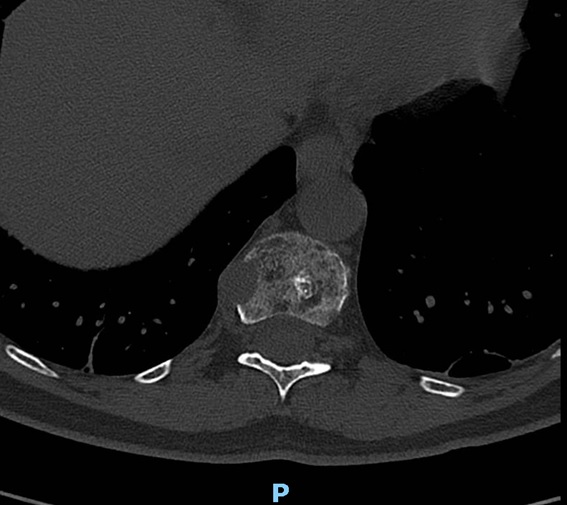

A su llegada a urgencias se realiza analítica complementa y una tomografía computerizada dorsolumbar objetivandose metástasis óseas cervical, dorsal D4, D6, D12 y afectación cuarto arco costal, se decide ingreso para estudio diagnosticándose un mieloma múltiple.

Se realiza radiografía de lumbar, dorsal y destaca chafamiento de D4 y una disminución radiodensidad ósea en todos los cuerpos vertebrales.